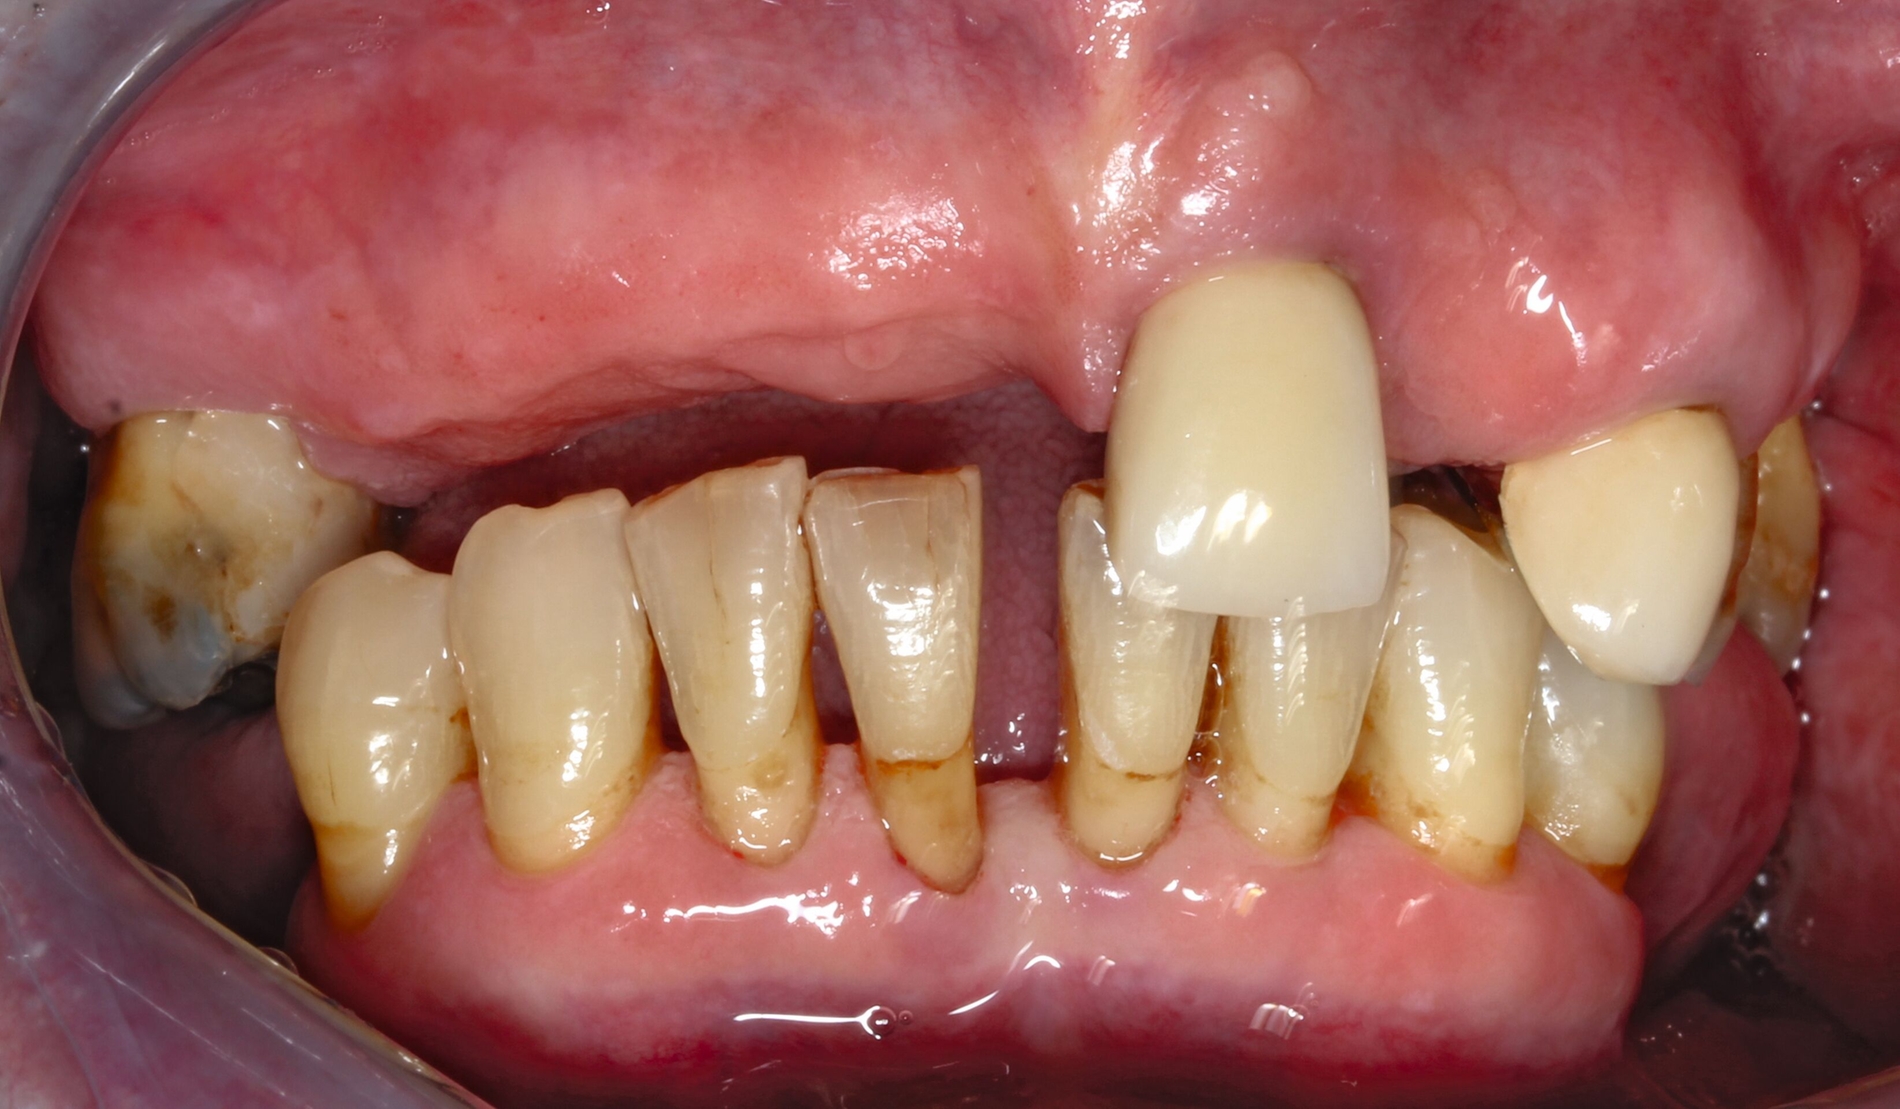

Voraussetzung für Wurzelkaries ist – wie der Begriff bereits andeutet – die Exposition von Wurzeloberflächen gegenüber einem kariogenen Milieu. Wegbereiter dazu sind Parodontalerkrankungen, die mit Attachmentverlusten einhergehen. Daten der aktuellen Mundgesundheitsstudie (DMS • 6) zeigen, dass etwa ein Viertel der 35- bis 44-Jährigen und zwei Drittel der 65- bis 74-Jährigen Attachmentverluste von 5 mm und mehr aufweisen [Eickholz et al., 2025].

Attachmentverlust ist mit der Vergrößerung der klinischen Interdentalräume verbunden, was zu vermehrter Retention von (kariogenen) Speiseresten führt und die Plaqueentfernung wie auch die Diagnostik erschwert. Gleichzeitig nimmt mit dem Anstieg der Parodontitisprävalenz der Pro-Kopf-Verbrauch von Medikamenten deutlich zu, darunter auch von solchen, die die Speichelsekretion und damit viele wichtige Schutzfunktionen in der Mundhöhle beeinflussen können [AOK, 2023].

Die Gruppe der alternden und alten Menschen ist jedoch eher heterogen, so dass das Alter in Jahren nicht mit Bedürftigkeit in Verbindung steht. So leben viele Menschen bis ins hohe Alter gesund und selbstständig, während andere bereits in früheren Phasen des Alterns erkranken und Unterstützung benötigen.

Obwohl sowohl die Wurzelkaries als auch die über das Initialstadium hinaus fortgeschrittene koronale Karies das Dentin betreffen, sind die Entstehungsbedingungen und Therapieoptionen sehr unterschiedlich. Einerseits ist die Wurzeloberfläche den kariogenen Bedingungen an der Grenzfläche zu stoffwechselaktiven Biofilmen sehr viel direkter ausgesetzt, und kariöse Läsionen sind oftmals so ungünstig lokalisiert, dass eine gute Füllungstherapie mit einem dauerhaften Verbund von Kompositen an der Zahnhartsubstanz schwierig ist. Andererseits, und das ist sehr entscheidend, ist sie aber auch sehr viel zugänglicher für nicht-invasive Therapieformen. Indikationsstellungen für die Behandlung koronaler Dentinkaries sind daher nicht einfach auf Wurzelkaries übertragbar. Während der Therapieentscheid bei koronaler Dentinkaries eher vorrangig bei der restaurativen Versorgung liegt, sollte bei Wurzelkaries die Arretierung in der Mehrzahl der Fälle die erste Option sein.

Ist die Läsion aktiv oder inaktiv? Die Beantwortung dieser Frage ist die Ausgangsbedingung für den Therapieentscheid. Wenngleich die Unterscheidung nicht immer einfach ist, ist eine weiche Textur bei Sondieren und eine deutliche Plaquebedeckung ein sicheres Zeichen für Kariesaktivität [Carvalho und Lussi, 2017]. Bei aktiven Läsionen sollten Lokalisation und Ausdehnung genau exploriert werden, was die Behandlungsoptionen wesentlich bestimmt (Abbildung 1). Bei inaktiven Läsionen ist keine restaurative Therapie erforderlich, jedoch sind risikoadaptierte Präventionsmaßnahmen angezeigt.